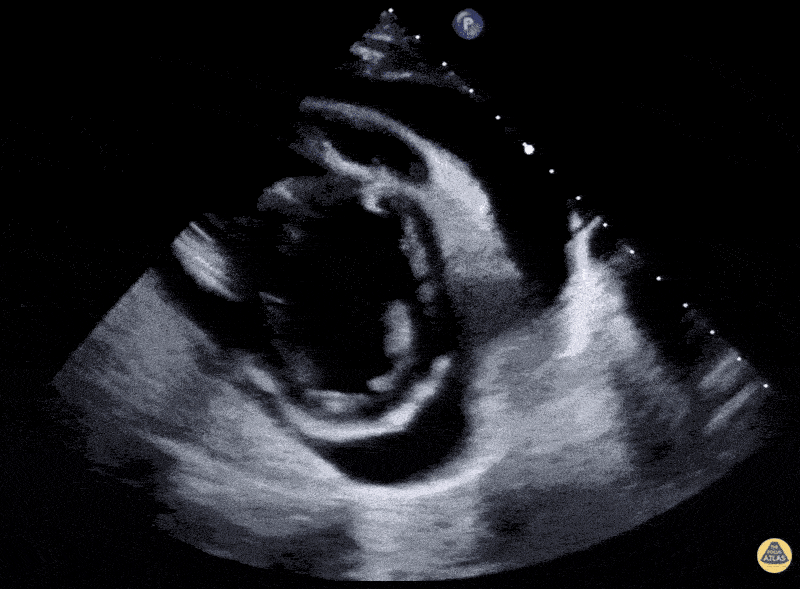

Pericardial Disease - SLE Pericardial Effusion in multiple views

20-year-old female patient, not known to have any medical illnesses. Presented to the ED complaining of generalized fatiguability, lightheadedness, exertional dyspnea, chest pain, palpitation, dry cough, and lower limb edema for 4 months, these symptoms has been intermittent and progressively worsening. Chest pain is position, aggravated by exertion and lying flat, relieved by rest and leaning forward. The patient also complains of hand joints pain and swelling, with temporary morning stiffness. The patient was tachycardic with a maintained BP. The patient’s clinical exam is positive for bilateral lung basal crepitation and bilateral lower limb pitting edema. Labs showed critically low Hb of 4.9 g/dL, ANA of 1:320, DAT+, and high agglutinin titer. Echo showed large pericardial effusion and evidence of early systolic collapse of right atrium (RA). The patient was diagnosed with systemic lupus erythematosus (SLE) and autoimmune hemolytic anemia with serositis. Hassan Alshaqaq, MBBS, Emergency Medicine Resident at King Saud University Medical City, Riyadh, Saudi Arabia. Twitter: @HassanAlshaqaq